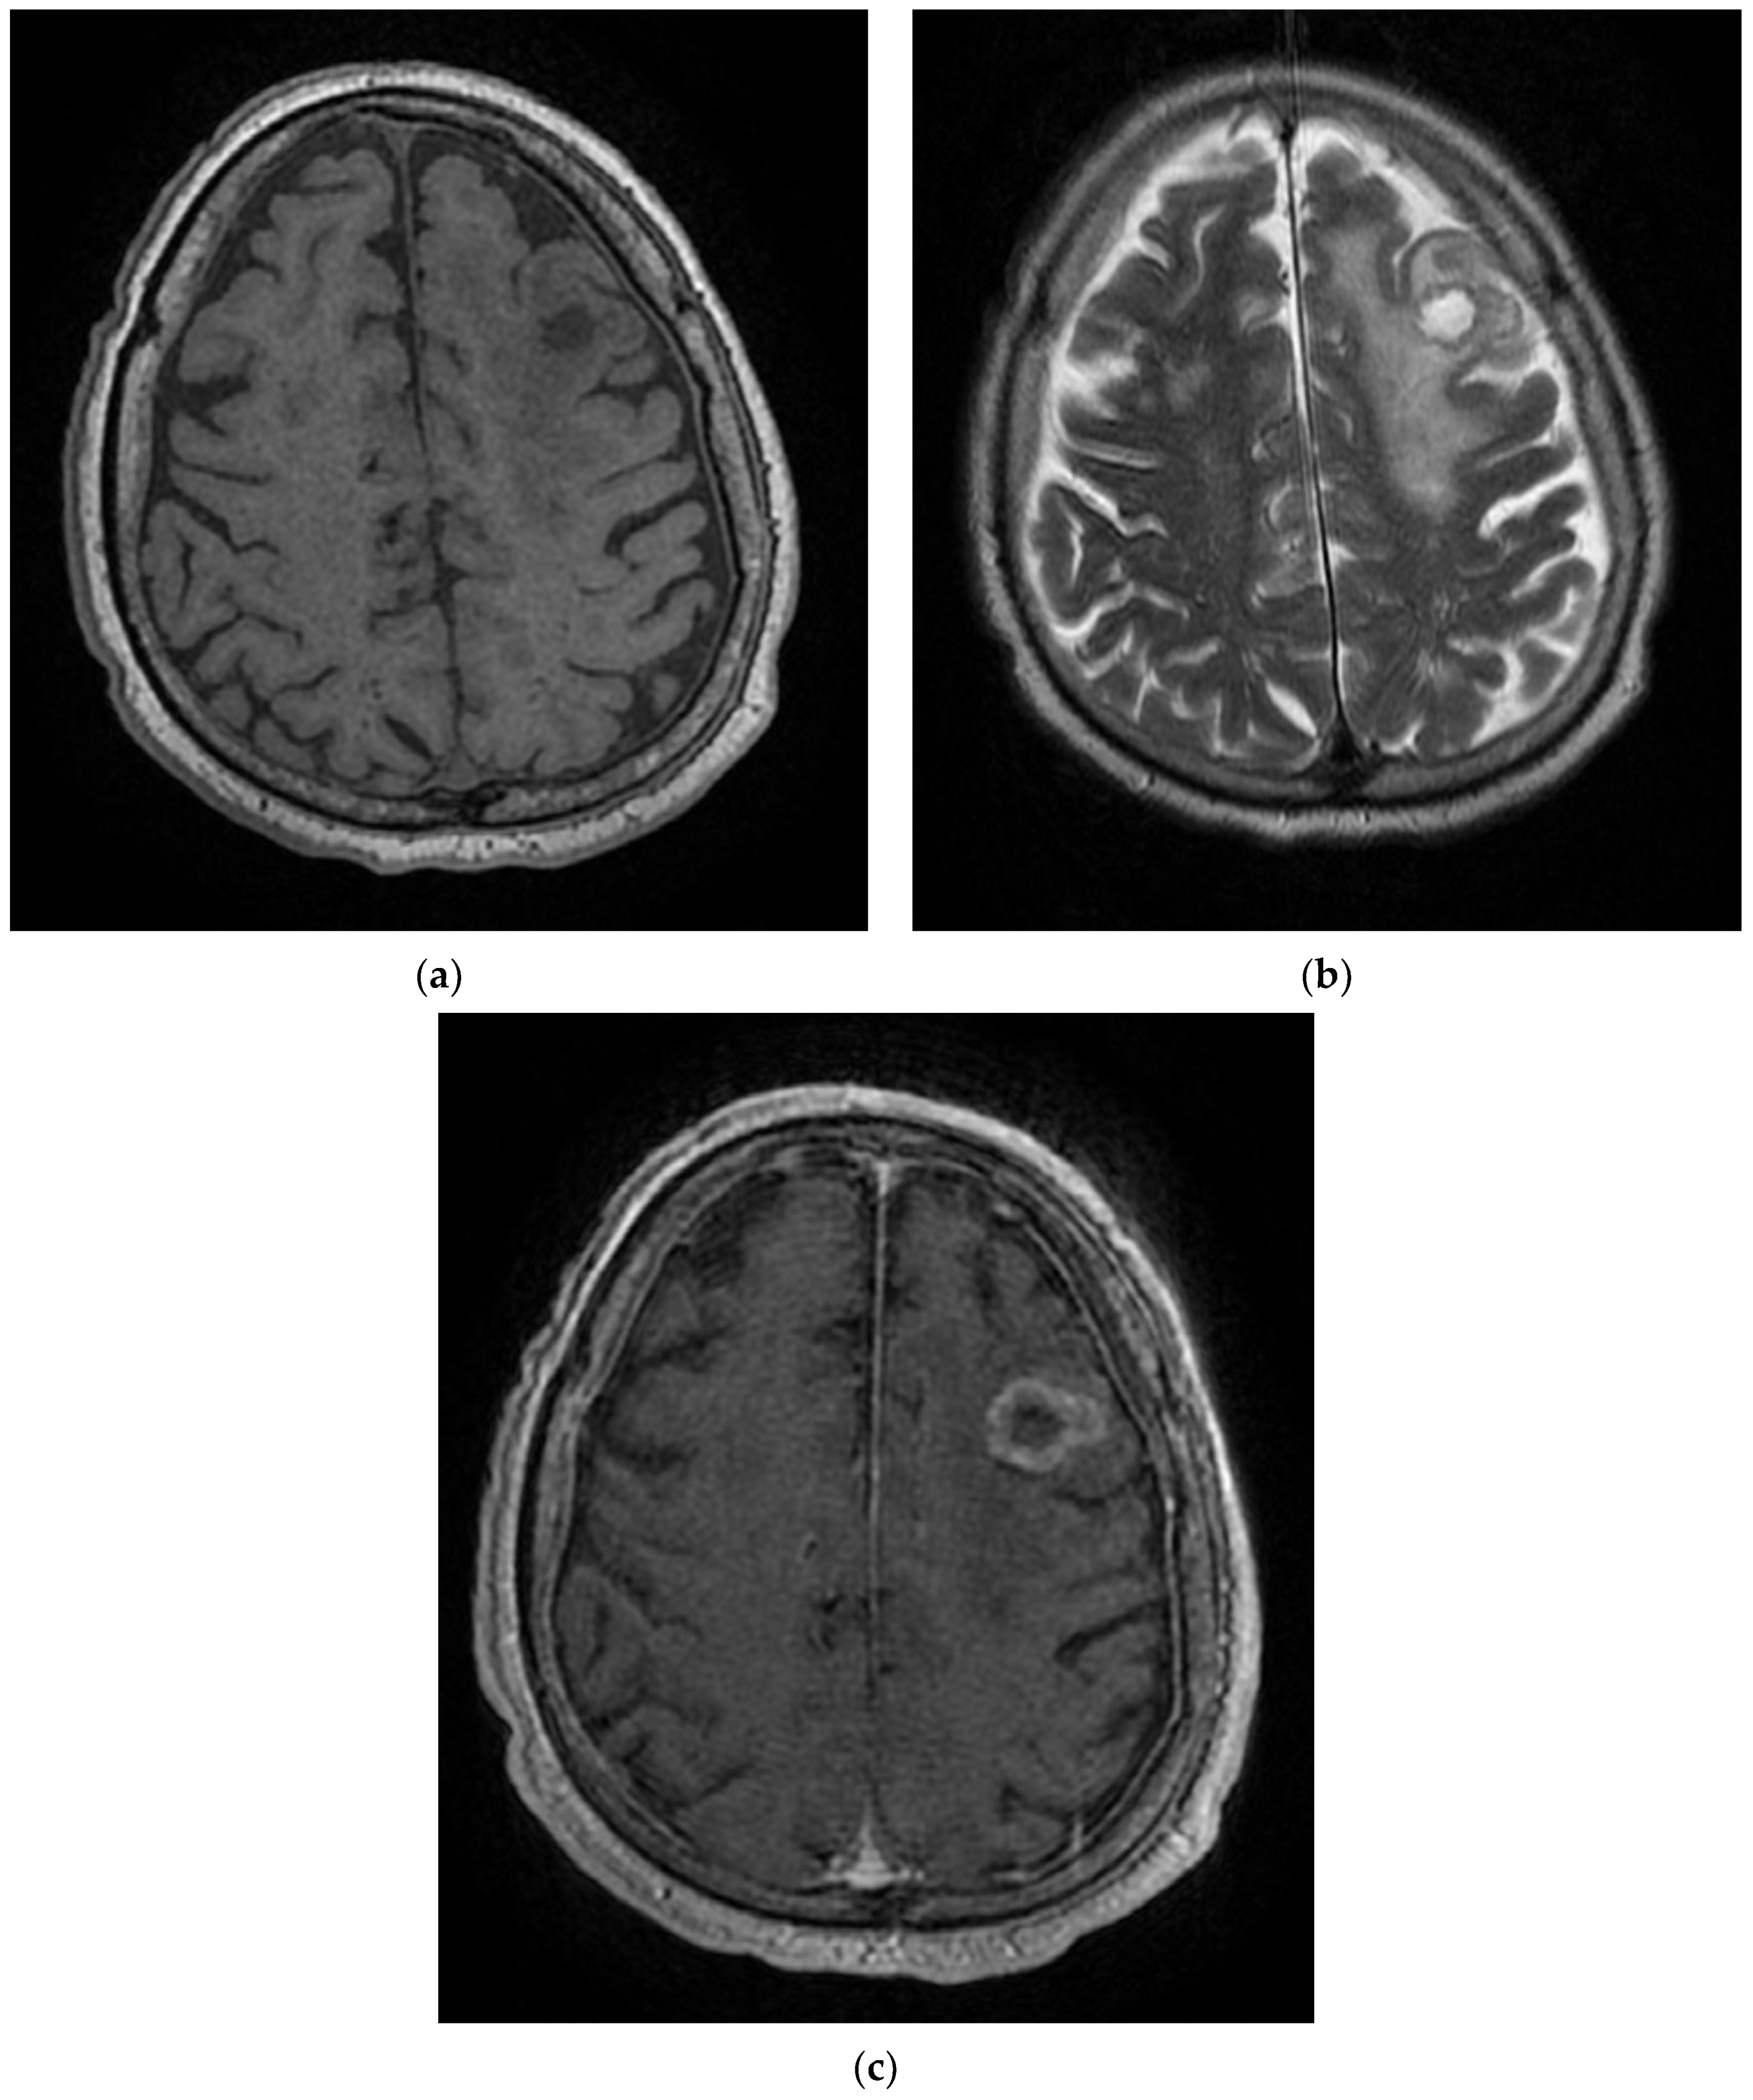

Figure 3. MRI images of the Case 3 patient reveal multiple centimetric lesions in T2/FLAIR hypersignal (a,b), with no diffusion restriction, disposed in a white hemispheric substance in the bilateral subcortical frontal–temporal–parietal area, as well as in the right cerebellar hemisphere, and supratentorial demyelinating lesions most probably with an ischemic vascular sublayer. Additionally, linear and curvilinear traces in SWAN signal (c,d), disposed in the left cortical parietal, frontal area–frontal cortical and left parietal hemosiderosis.

On day 6, the patient underwent a native brain MRI showing multiple infra- and juxta-centimetric lesions in hyper seminal T2/FLAIR, without diffusion restriction, bilaterally arranged in the hemispheric white matter subcortical frontal–temporal–parietal, as well as in the right cerebellar hemisphere and supratentorial demyelinating lesions, most likely with ischemic vascular substrate and linear and curvilinear tracts in a SWAN (susceptibility-weighted angiography)-like manner, and left-frontal and left-parietal cortical hemosiderosis (Figure 3).